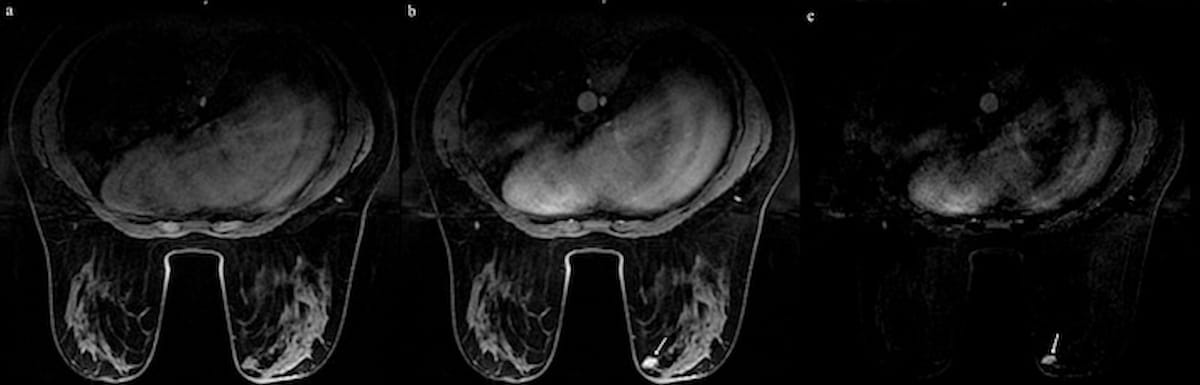

While ultrasound could not differentiate between an intraductal papilloma (IDP) and ductal secretion in a 23-year-old patient, abbreviated MRI revealed a 17 x 8 mm enhancing solid lesion (see white arrow), which was subsequently confirmed via a histopathology exam as an IDP. (Images courtesy of the European Journal of Radiology.)

For a new retrospective study, recently published in the European Journal of Radiology, researchers compared the use of abbreviated MRI (AB-MRI) and full diagnostic breast MRI (FDB-MRI) in 62 patients (mean age of 46.05) who had inconclusive ultrasound findings. The AB-MRI protocol consisted of fat-suppressed pre-contrast T1 MRI, initial post-contrast T1 MRI and subtracted images from FDB-MRI, according to the study.